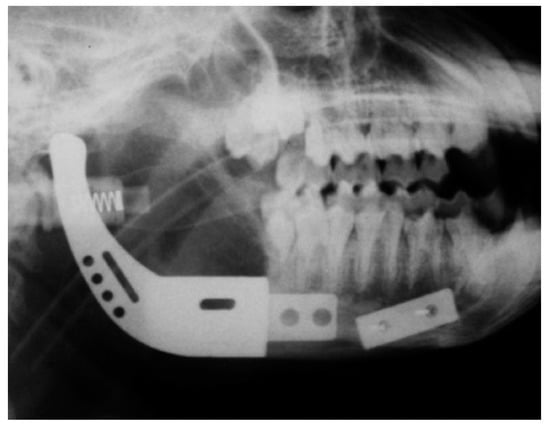

- Goh, B.T.; Lee, S.; Tideman, H.; Stoelinga, P.J. Replacement of the condyle and ascending ramus by a modular endoprosthesis in Macaca fascicularis—Part 1: a clinical and radiographic study. J. Oral Maxillofac. Surg. 2009, 67, 1392–1400. [Google Scholar] [CrossRef] [PubMed]